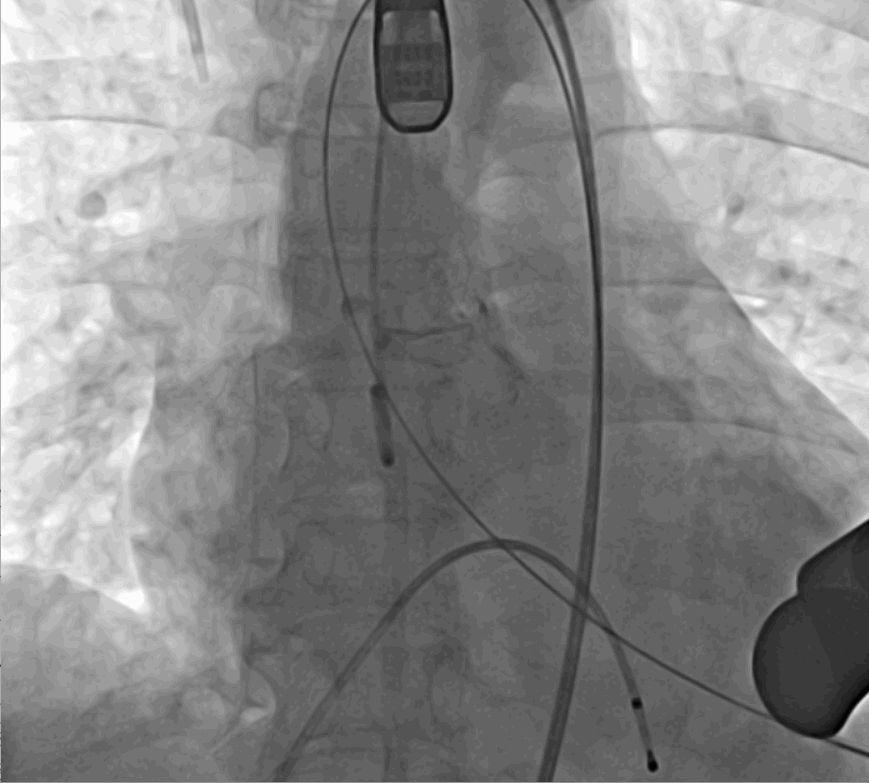

手術(shù)采用經(jīng)心尖入路,對患者進(jìn)行全麻后,在左側(cè)心尖處做3-4cm微創(chuàng)手術(shù)切口,在DSA及超聲引導(dǎo)下手術(shù)順利完成。從導(dǎo)入器械到完成瓣膜置入,僅耗時約10分鐘。術(shù)后即刻主動脈瓣返流程度由術(shù)前大量返流轉(zhuǎn)為消失,患者于導(dǎo)管室拔除氣管插管,次日由ICU轉(zhuǎn)入普通病房。

術(shù)后DSA影像